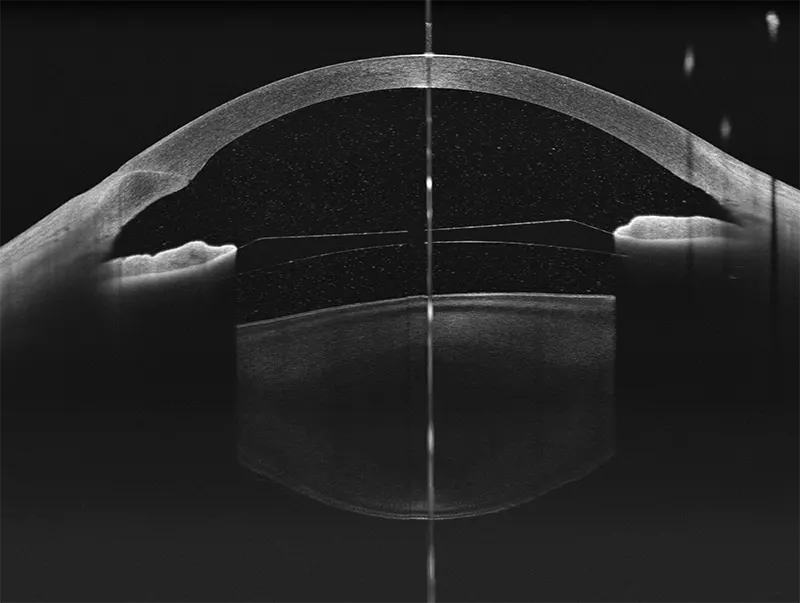

- Profundidad de escaneo de 12 mm, ideal para casos complejos como estafiloma miopía

Yalkaid (YG-100K) es una nueva generación de SS-OCT con una velocidad de 100 kHz. Su principal ventaja radica en la tecnología SS de rango completo, que permite una profundidad de escaneo de 12 mm para el vítreo, la retina y la coroides, y una extraordinaria de 15 mm para el segmento anterior. La resolución óptica de <6 micrones del dispositivo garantizan una observación detallada de las estructuras anteriores y posteriores.

Galería OCTs del TowardPi Yalkaid